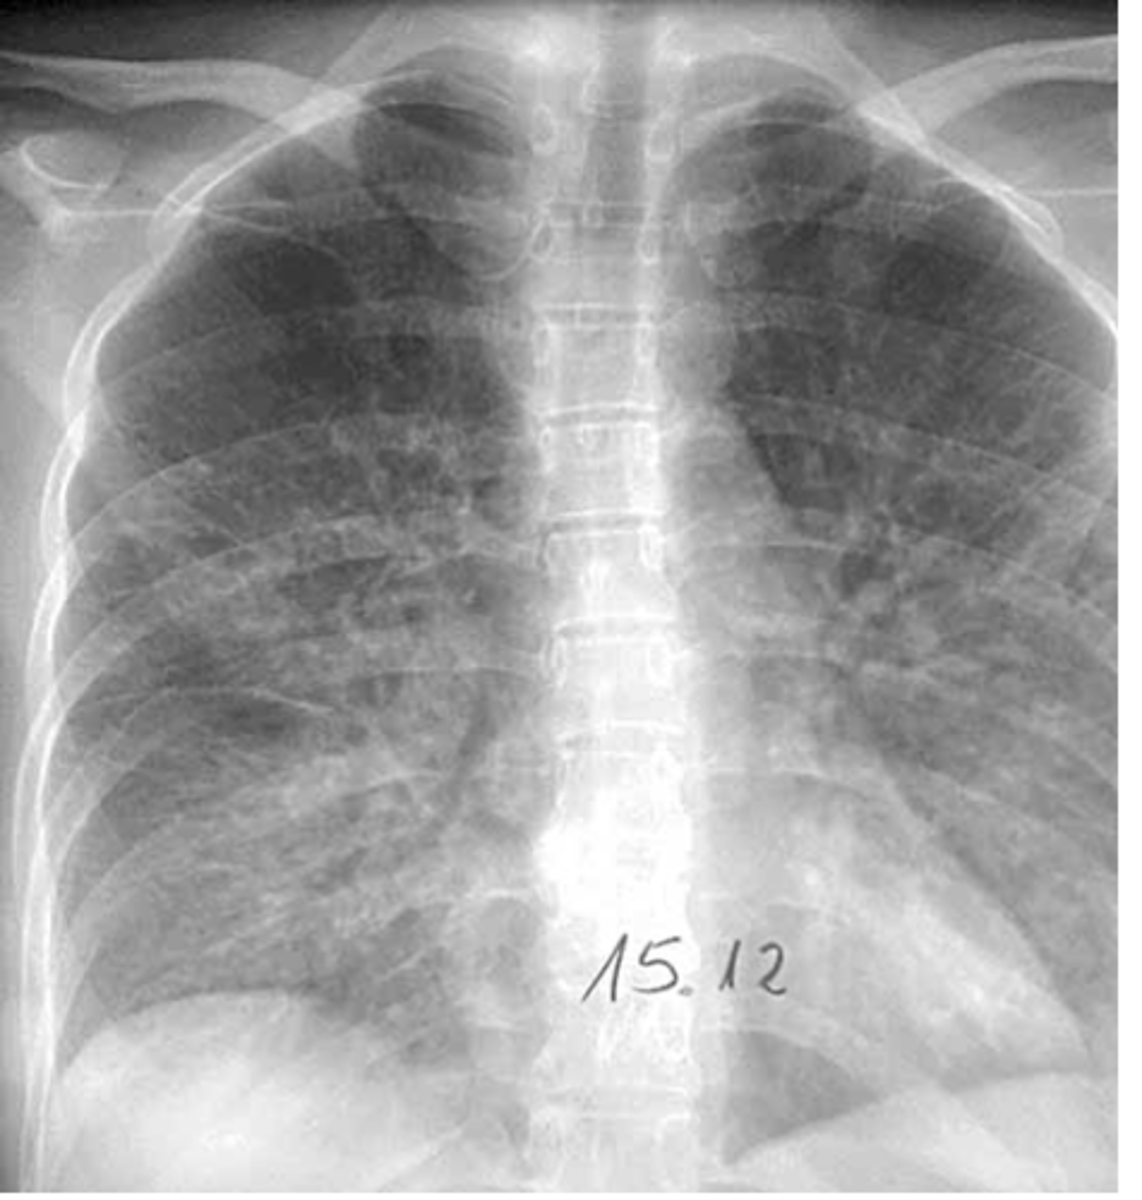

What do interstitial infiltrates look like and what are some causes? IS this sign specific or non specific?

caused by acute and chronic disease processes that affect the tissue outside of the alveoli.

Interstitial processes are usually diffuse & are seen as thin white lines. May appear honeycombed (reticular)

Interstitial infiltrates are nonspecific as they can be caused by many processes such as CHF, pulmonary fibrosis, collagen vascular diseases, etc.

<p>caused by acute and chronic disease processes that affect the tissue outside of the alveoli.</p><p>Interstitial processes are usually diffuse &amp; are seen as thin white lines. May appear honeycombed (reticular)</p><p>Interstitial infiltrates are nonspecific as they can be caused by many processes such as CHF, pulmonary fibrosis, collagen vascular diseases, etc.</p>